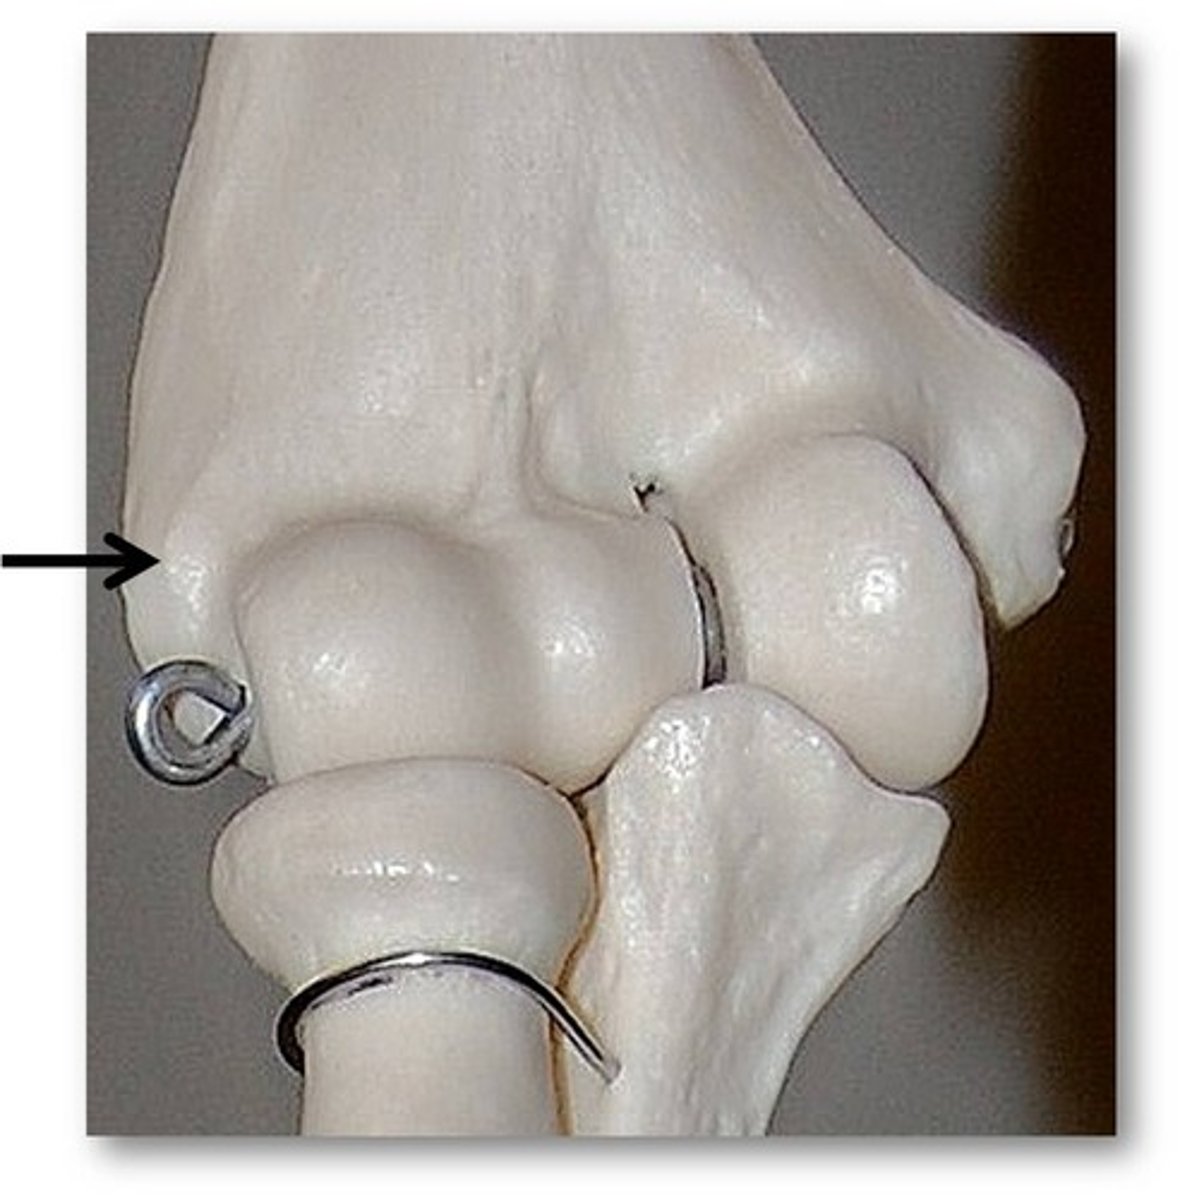

medial condyle of femur

lateral condyle

medial epicondyle

lateral epicondyle

intercondylar fossa

tibial plateau

medial condyle of tibia

lateral condyle of tibia

intercondylar eminence of tibia